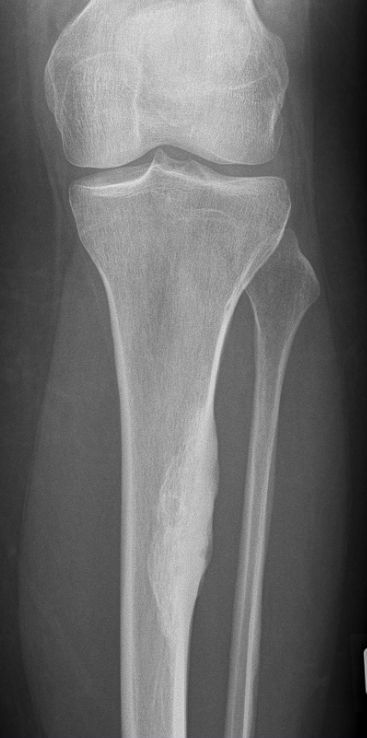

| Osteoidosteom | Typisch ist eine zentrale Aufhellung, der Nidus, mit perifokaler Sklerosierung. Der Nidus kann z.B. durch Thermoablation beseitigt werden.. | 67-jährige Frau mit HNO-Tumor. Im

| ossifizierendes Fibrom | ![]() 40jährige Landwirtin mit Mammakarzinom pT1c M8 pN1a (3/23) M0 G2, ER 12, PR 12, Her2neu: ++, FISH –, L1 V0, KI 67:20%, Pn0 - 13.05.14 Ablatio und Axilladissektion Level 1 und 2 - Histologie: 8 Herde 0,2 - 1,8 cm invasives mikropapilläres Karzinom, DCIS 70 mm - Ab 06/2014 4 x EC, dann 12 x Paclitaxel Chemotherapie |

![]() Keine Veränderung innerhalb von 18 Monaten | |||||||||||||